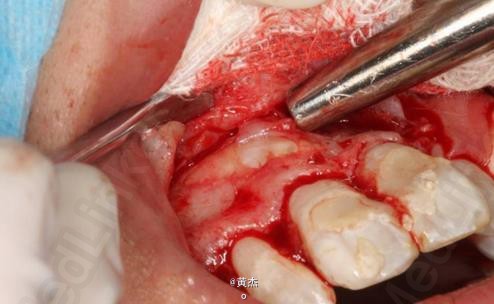

诊断:11、21根尖周炎。处理:11、21开髓无活力,大量血性渗出,根管无法测量。于是转诊口腔外科。术前和患者签知情同意书。给患者讲明外科手术有可能失败,最终拔除11、12、21的可能性。口腔外科处理:拔除13.。发现 11牙根几乎完全吸收、21唇侧牙根也被13牙冠压迫吸收到根中1/3。于是术中行11、21MTA根尖区封闭。12暂不做处理,观察半年后考虑进一步治疗方案。